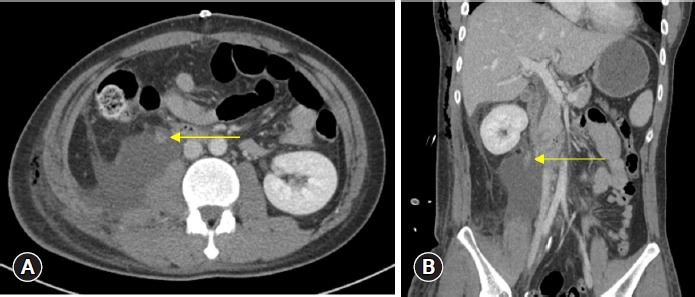

Traumatic ureteral injuries account for fewer than 1% of traumatic urologic injuries, and those caused by blunt trauma are even rarer than those caused by penetrating trauma. The symptoms associated with ureteral injury may be subtle, with or without hematuria, making it difficult to diagnose. We report the case of a 31-year-old man with a delayed diagnosis of proximal ureter injury after abdominal blunt trauma sustained in a motorcycle traffic accident. The patient underwent emergency laparotomy on admission for liver injury, mesenteric injury, and resultant hemoperitoneum. On postoperative day 6, he underwent angioembolization for suspected remnant intra-abdominal bleeding. Persistent symptoms of flank pain and leukocytosis led to follow-up imaging studies that revealed proximal ureter injury, and the patient underwent unilateral nephrectomy. This case stresses the importance of clinical suspicion for genitourinary injuries in the presence of abdominal trauma.

输尿管外伤在泌尿系统外伤中所占比例不到 1%,钝器外伤造成的输尿管外伤比穿透性外伤造成的输尿管外伤更为罕见。输尿管损伤的相关症状可能很隐蔽,伴有或不伴有血尿,因此很难诊断。我们报告了一例因摩托车交通事故造成腹部钝性外伤而导致输尿管近端损伤诊断延迟的 31 岁男性病例。患者入院时因肝脏损伤、肠系膜损伤和腹腔积血接受了急诊开腹手术。术后第 6 天,他因怀疑腹腔内残余出血而接受了血管栓塞术。持续的侧腹疼痛和白细胞增多症状导致后续影像学检查发现输尿管近端损伤,患者接受了单侧肾切除术。本病例强调了临床怀疑腹部创伤时泌尿生殖系统损伤的重要性。